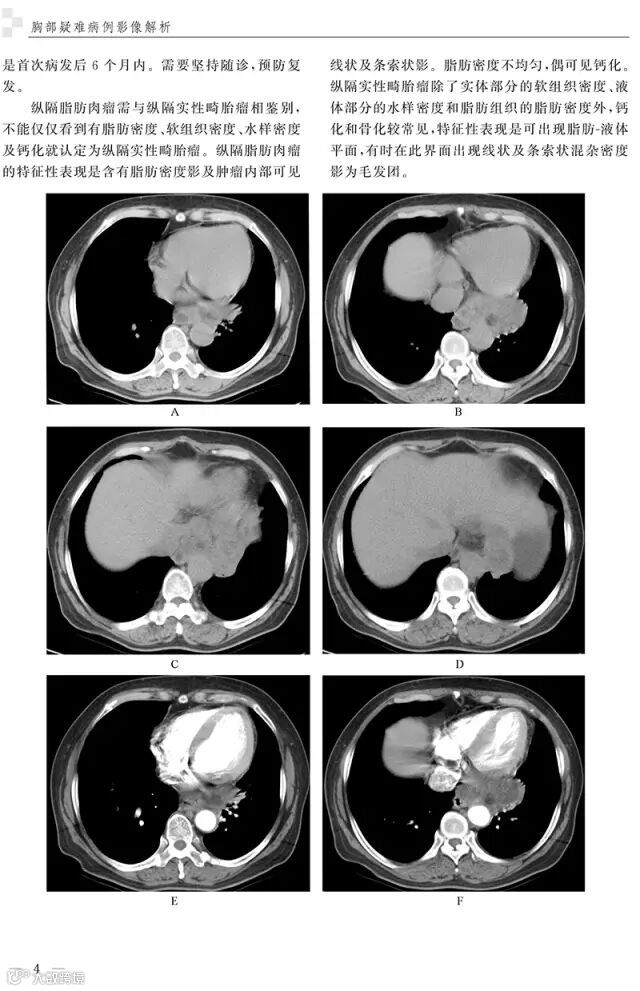

精彩插图

病例2 后纵隔脂肪肉瘤3